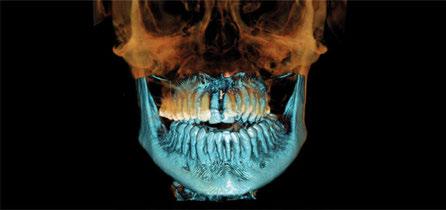

-CBCT para obtener imágenes en 3D del caso.

-Protocolo de planificación digital del caso mediante RealGUIDE® (STL+DICOM) (Figura 4) (Cuadro 1).

En la exploración radiográfica (OPG, CBCT) observamos la existencia de pérdida ósea interproximal, lesión apical a nivel de la raíz mesial del 27 y el cordal del primer cuadrante incluido y neumatización sinusal del primer y segundo cuadrante.

En el CBCT observamos pérdida ósea posterior superior debida a la neumatización de los senos maxilares izquierdo y derecho. También podemos observar disponibilidad ósea apical suficiente en dientes antero-superiores para la realización de una Implantología inmediata y corticales vestibulares y palatinas conservadas.